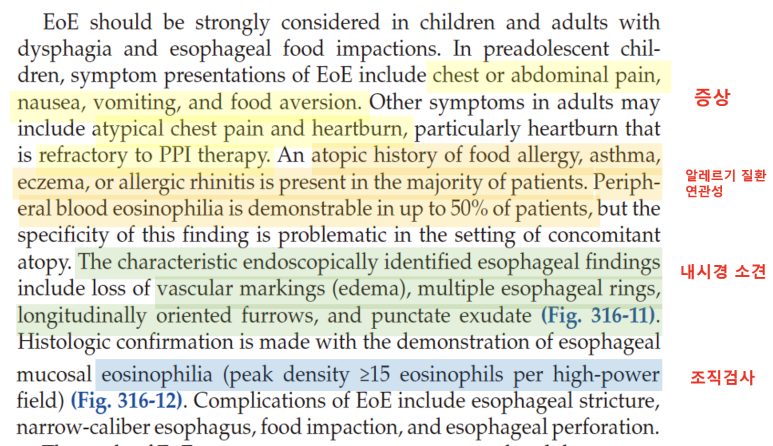

오늘부터 호산성 식도염에 대해서 알아보겠습니다.글을 쓰다 보니, 호산구의 식도염에 대해서 언급해야 할 것이 생각보다 많아 GERD처럼 파트를 나누어 설명하고 싶습니다.Introduction우선 해리슨의 교과서에서 호산성 식도염에 대해서 어떻게 기술하고 있는지 봅시다. 호산성 식도염은 말 그대로 식도에 염증이 생기는 질환입니다. 대표적인 증상은 흉통, 복통, 오심, 복통, 복통, 복통, 이해 곤란, 성인의 경우는 PPI에도 반응이 없는 heartburn(가슴이 타는 듯한 느낌)이 주된 증상입니다. 알레르기 질환(음식 알레르기 천식 두드러기, 알레르기 비염 등)의 대부분이 환자에 따른, 말초 혈액에서 호산성의 수치가 올라가는 경우가 환자의 50%까지 보고되고 있습니다. 내시경 소견은 스코프 스코프(스코프)당 15개 이상의 호산성이 확인되고 진단 가능합니다.

(왼쪽) 내시경소견, (오른쪽) 조직검사소견증상에서 하나씩 살펴보겠습니다.유럽 가이드라인에서는 소아와 성인의 증상을 나누어 설명을 하고 있었습니다. 소아의 경우 역류가 주된 증상으로 구토, 복통, 식사 거부 등의 증상이 있으며 성인의 경우 고형물 섭취가 어렵고 흉통이 일어나는 것으로 알려져 있습니다.

미란성 식도염의 경우 붉은 발적과 발적병변 주변에 부종 소견이 있는 반면 호산구 식도염의 경우 Furrow와 ring이 특징적인 소견입니다.

주의할 점은 내시경 소견으로 호산구 식도염을 진단해서는 안 된다는 것입니다. 예를 들면, EREFS 시스템이라는 것이 있습니다. 이 점수체계는 호산구 식도염 내시경 소견의 중증도를 점수화하여 기술하는 기준입니다. 중요한 것은 이 점수가 높다고 해서 호산구 식도염의 disease activity가 높다고 이야기하거나 관해됐다는 것을 말할 수 없다는 것입니다.

조직검사소견은 호산구가 H PF당 15개 이상 검출되는 것이 가장 중요하며, ECM 공간이 더욱 증가하고 basal zone hyperplasia가 동반되는 특징을 가지고 있습니다.

메커니즘 호산구 식도염의 발생 메커니즘을 알아보겠습니다IgE와 관련된 음식알레르기, 알레르기 비염, 천식, 습진과 같은 알레르기 관련 질환이 호산구 식도염 환자에게 자주 보고되고 있습니다.